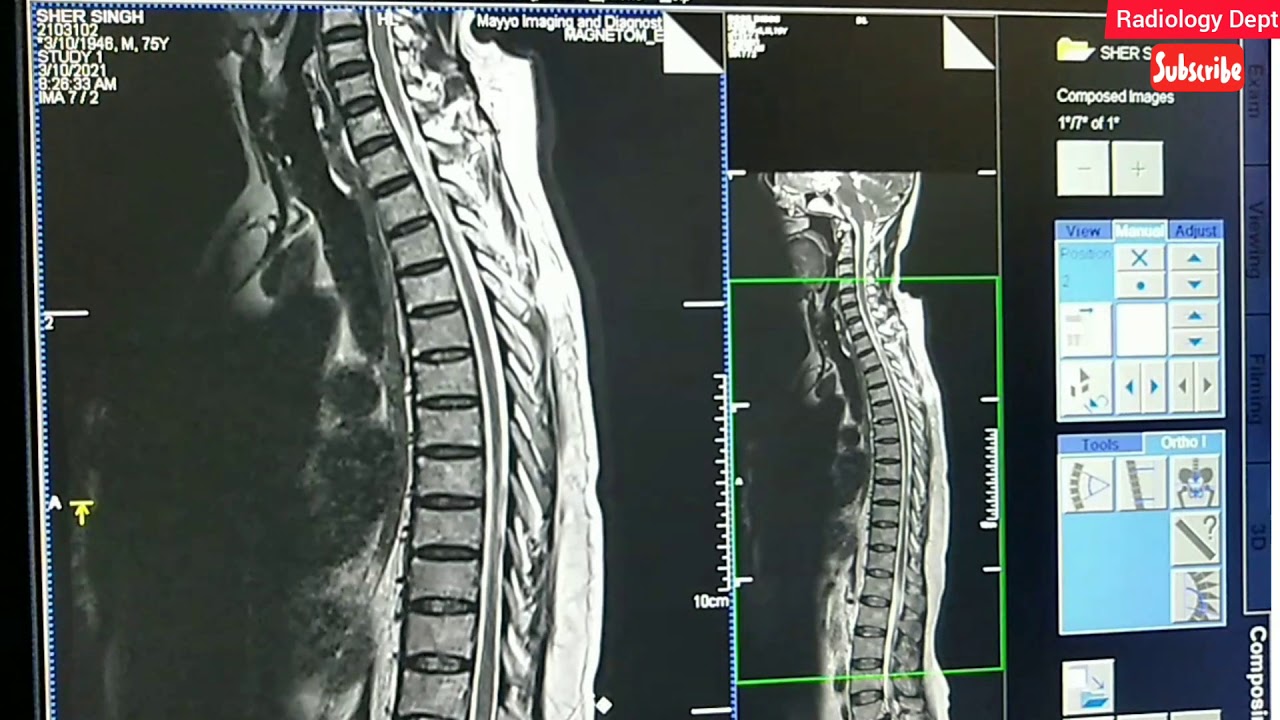

Viral MRI WHOLE SPINE

Here Whole Spine Screening Mri || Whole Spine Screening Composing | #Mriwholespine #Spine #Backache #Pain